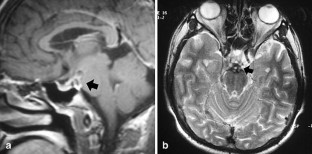

Brucellosis is a multisystem disease that may present with a large spectrum of clinical manifestations. Only five cases of intracranial aneurysm formation and/or subarachnoidal hemorrhage associated with brucellosis have been reported. In this paper, we take the opportunity to review these reports and present a new case of basilar artery aneurysm and subarachnoidal hemorrhage due to brucellosis.

Fig. 2